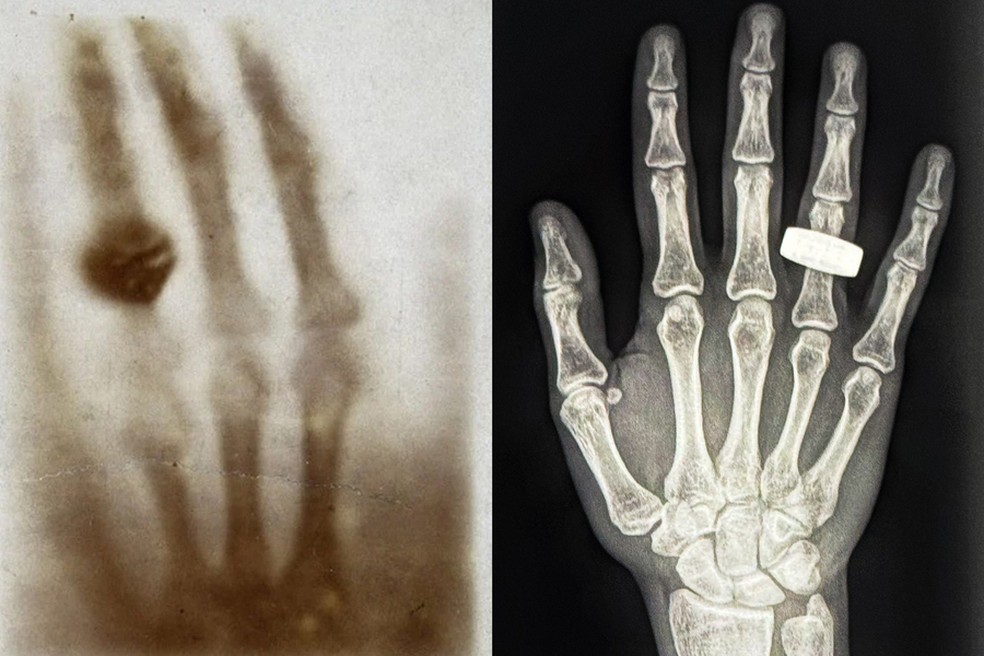

O feito integra o projeto “SpaceXray” e faz referência ao primeiro raio-X já tirado na história, há aproximadamente 130 anos. Na ocasião, o físico alemão Wilhelm Roentgen enquadrou na varredura a mão de sua esposa, Anna Ludwig, que também portava uma aliança em seu dedo. Veja a comparação entre as duas imagens:

Na foto à esquerda, está o primeiro raio-X médico já tirado, há 130 anos. À direita, a primeira imagem de raio-X tirada no espaço — Foto: Reprodução/X (@satofishi)